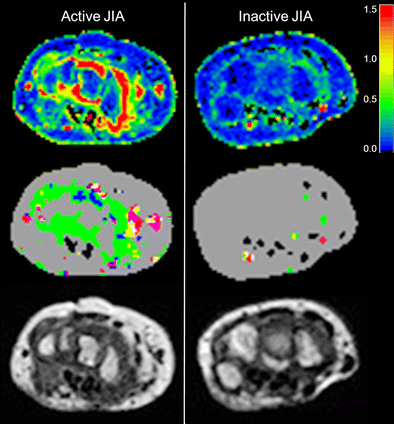

Explanation of the time-intensity-curve shapes and their color coding. Time-intensity-curve shape 7 is not shown as this class includes all the various shapes that cannot be classified as 1-6. Examples are given in [21]

The difference between clinically active juvenile idiopathic arthritis in an 8-year-old boy (left) and inactive juvenile idiopathic arthritis in a 13-year-old girl (right) on maximum enhancement maps (upper row), time-intensity-curve shape maps (middle row), and T1-weighted dynamic contrast-enhanced-maps (bottom row). The colors of the time-intensity-curve shapes correspond with the time-intensity-curve shapes as mentioned in Fig. 2. Scan parameters: axial plane, echo time 6.9 ms, repetition time 9.9 ms, voxel size 1.0 mm × 1.0 mm × 1.5 mm, temporal resolution 15.5 s